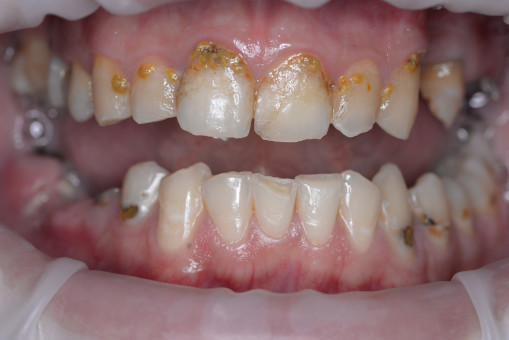

А прежде, чем вы посмотрите фотографии «до» и «после» лечения слизистой оболочки полости рта, проведенных в нашей клинике, хочу поблагодарить большое количество наших пациентов, которые поверили, прониклись нашей концепцией, и мы вместе, именно вместе победили болезни десны, гингивит и пародонтит!

До/после лечения